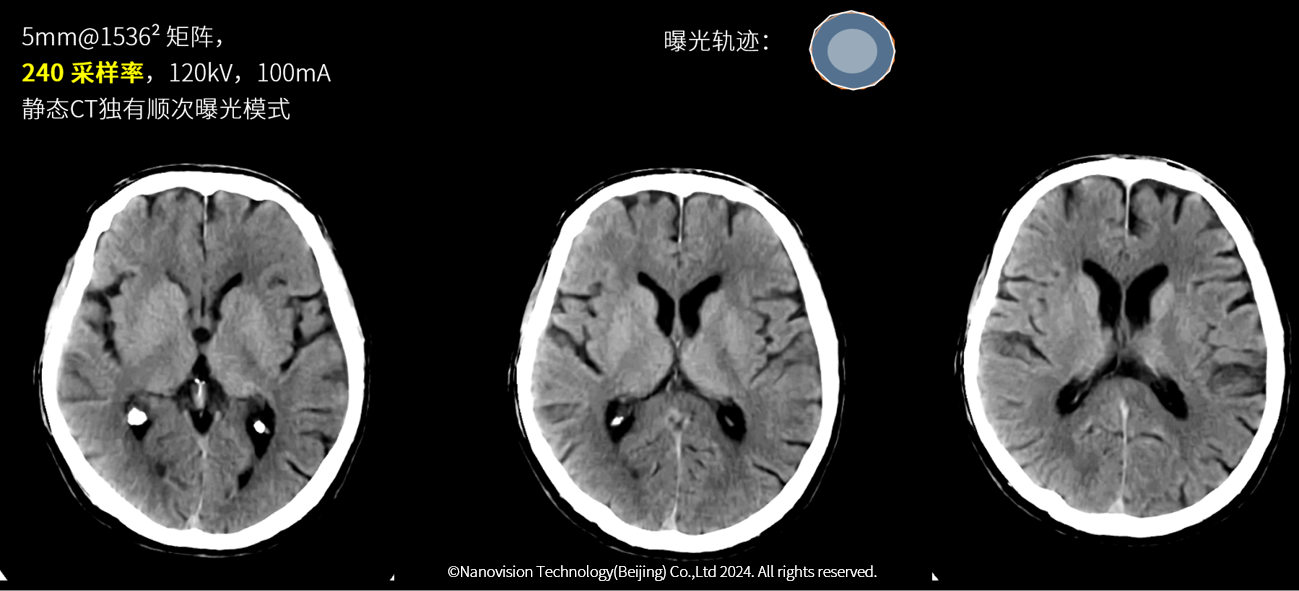

静态CT超高精度成像高清显示颅脑神经核团